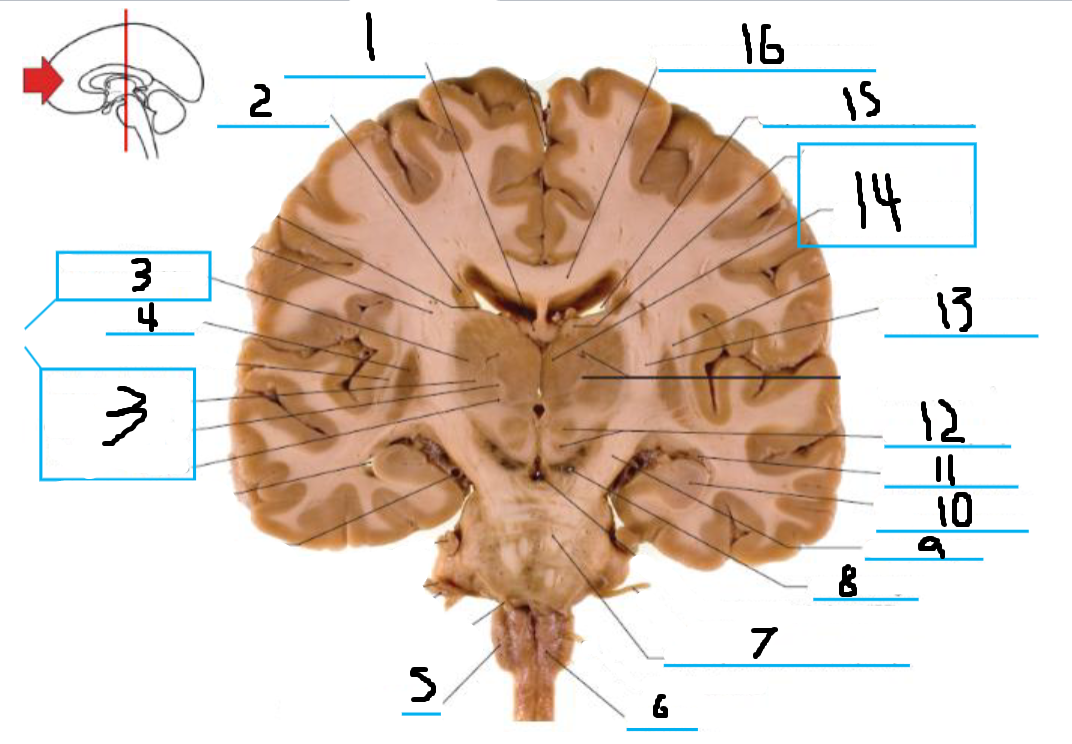

#1 is the:

Cingulate Gyrus

#2 is the:

Septum Pellucidum

#3 is the:

Lateral Ventricle

#4, #7, and #12 is the:

Fornix

#5 is the:

Third Ventricle

#6 is the:

Anterior Commissure

#8 and #11 is the:

Amygdala

#9 is the:

Hypothalamus

#10 is the:

Mammillary Body

#13 is the:

Insula

#14 is the:

Globus Pallidus

#15 is the:

Putamen

#16 is the:

Internal Capsule

#17 is the:

Caudate

#18 is the:

Corpus Callosum